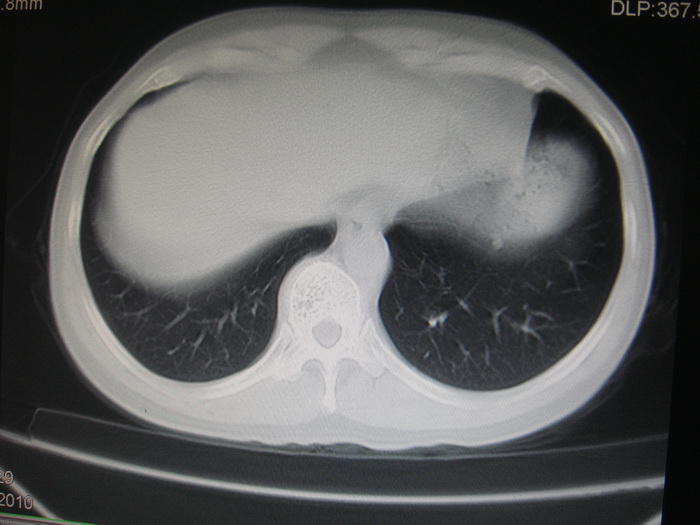

标题: CT28366:男性,45岁,偶尔发现右颈部肿块行胸部CT扫描。 [打印本页]

男性,45岁,偶尔发现右颈部肿块行胸部ct扫描。

两肺多发结节灶及纵膈淋巴结肿大考虑为转移

两肺多发性转移瘤,纵隔淋巴结转移。

两肺多发性转移瘤,纵隔淋巴结转移。食道中上段管壁似乎增厚,作相关检查。

两肺多发性转移瘤,前上纵隔淋巴结转移。